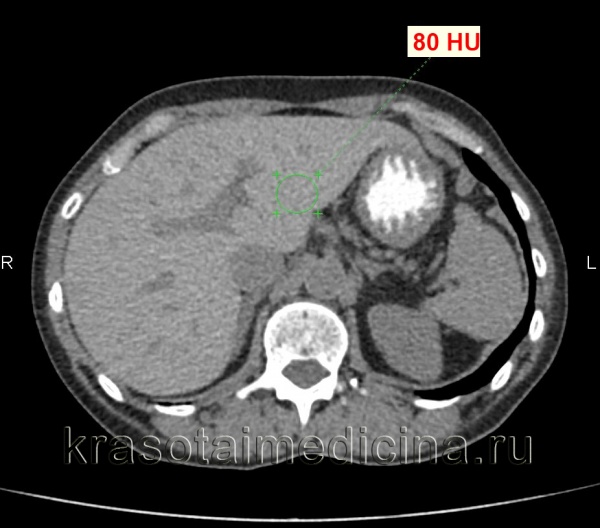

КТ органов брюшной полости. Диффузное повышение плотности печени до 80 ед. Хаунсфилда (преконтрастное изображение) за счет диффузного отложения железа.